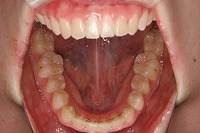

下顎 | ![]() |

![]() |

反対咬合を主訴に来院された、右側唇顎裂の10歳6ヵ月の女の子です。診断「右側唇顎口蓋裂で反対咬合を伴う」1期治療で反対咬合の解消と上顎の前歯の並びを修正しました。2期治療は抜歯をせず治療を行いました。